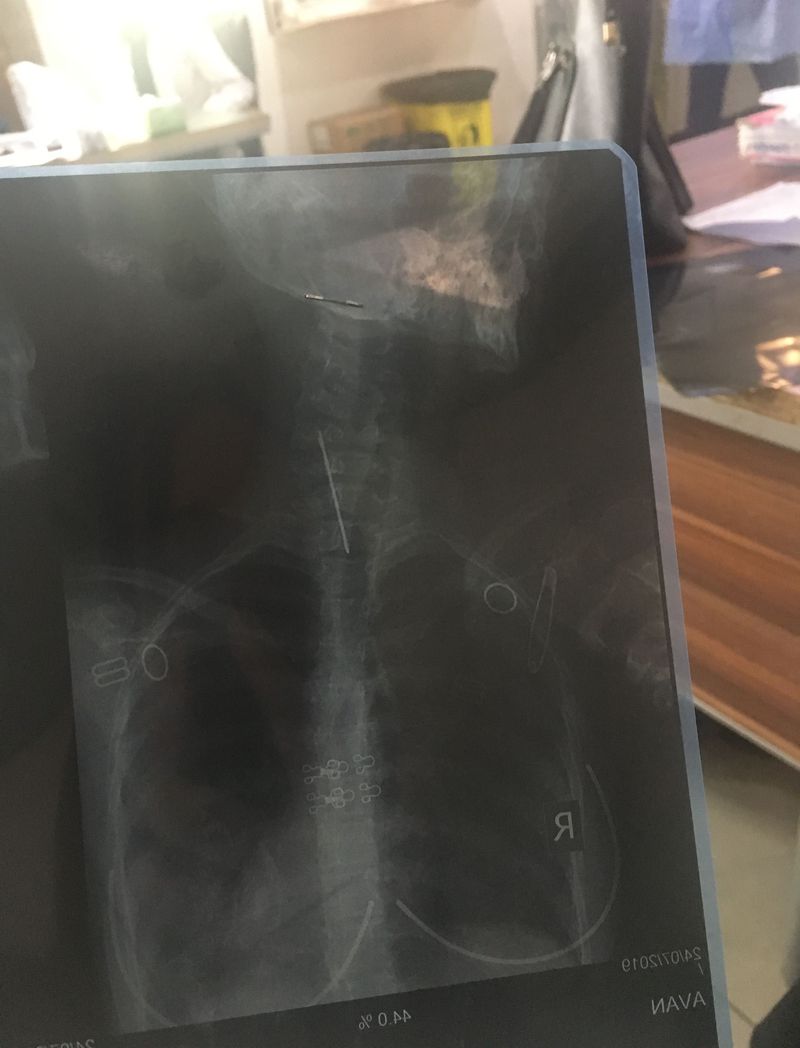

At emergency a15 yrs old girl swallowed a pin with rice but after taking another x-ray it disappeared

Isn't it in the abdominopelvic x-ray?

It can’t disappear😄 May be the pin is not in her(superpose I mean)